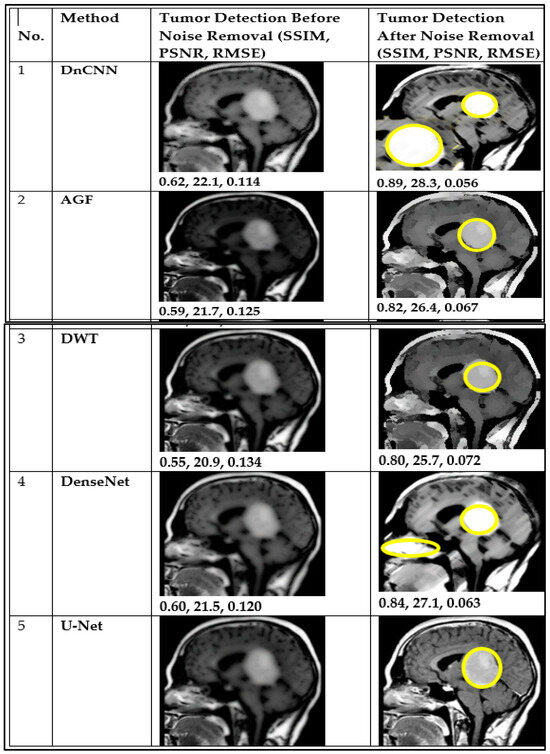

| 1 | DnCNN | 0.62 | 0.89 | 22.1 | 28.3 | 0.114 | 0.056 |

| 2 | AGF | 0.59 | 0.82 | 21.7 | 26.4 | 0.125 | 0.067 |

| 3 | U-Net | 0.57 | 0.81 | 21.1 | 26.0 | 0.128 | 0.069 |

| 4 | DWT | 0.55 | 0.80 | 20.9 | 25.7 | 0.134 | 0.072 |

| 5 | DenseNet | 0.60 | 0.84 | 21.5 | 27.1 | 0.120 | 0.063 |